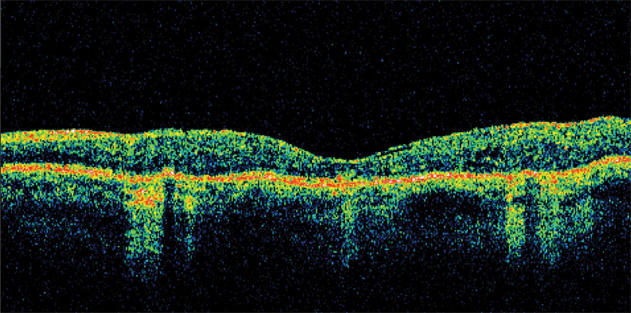

This optical coherence tomography (OCT) scan shows an eye with diabetic macular edema.

The patient returned in November 2006, and her acuity was stable at 20/250 (32 letters) OS, but the foveal thickness had improved to 155 μm. There were mild cystic changes apparent on the OCT cross section.

At her next visit in March 2007, the patient's visual acuity had improved to 20/160 (43 letters). The foveal thickness remained stable at 158 μm with mild cystic changes.

By August 2007, the patient's acuity had improved to 20/125 (46 letters) and the foveal thickness had increased to 178 μm, again with mild cystic changes.